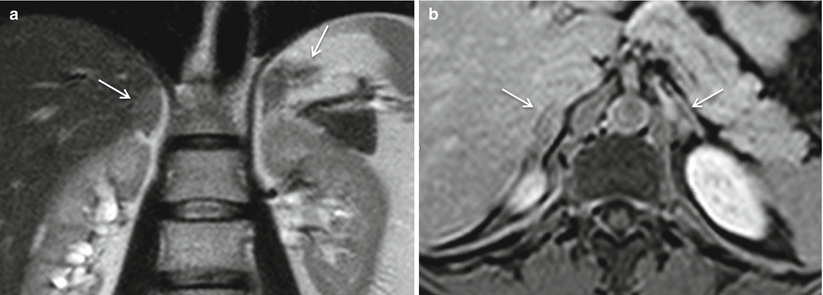

Adrenal hyperplasia. Diffuse enlargement of both adrenal glands on coronal T2-weighted MRI (a) and axial T1-weighted post-gadolinium (b) images (white arrows)

As the “hyperplasia” term stands, a common imaging finding in CAH is a diffuse enlargement of both adrenal glands, while preserving their typical shape and heterogeneous post-contrast enhancement on CT and MRI (Figs. 12.1, 12.2, and 12.3) [1, 6–14]. Interestingly, adrenal size is positively correlated with plasma concentration of dehydroepiandrosterone sulphate [15]. However, it is very important to note that an imaging finding of normal adrenal glands does not exclude the possibility of CAH [16–18]. Also, imaging appearance in CAH may have no difference from ACTH-dependent Cushing’s syndrome (Figs. 12.4 and 12.5), in which fertility is often impaired due to hypercortisolism (Table 12.1).